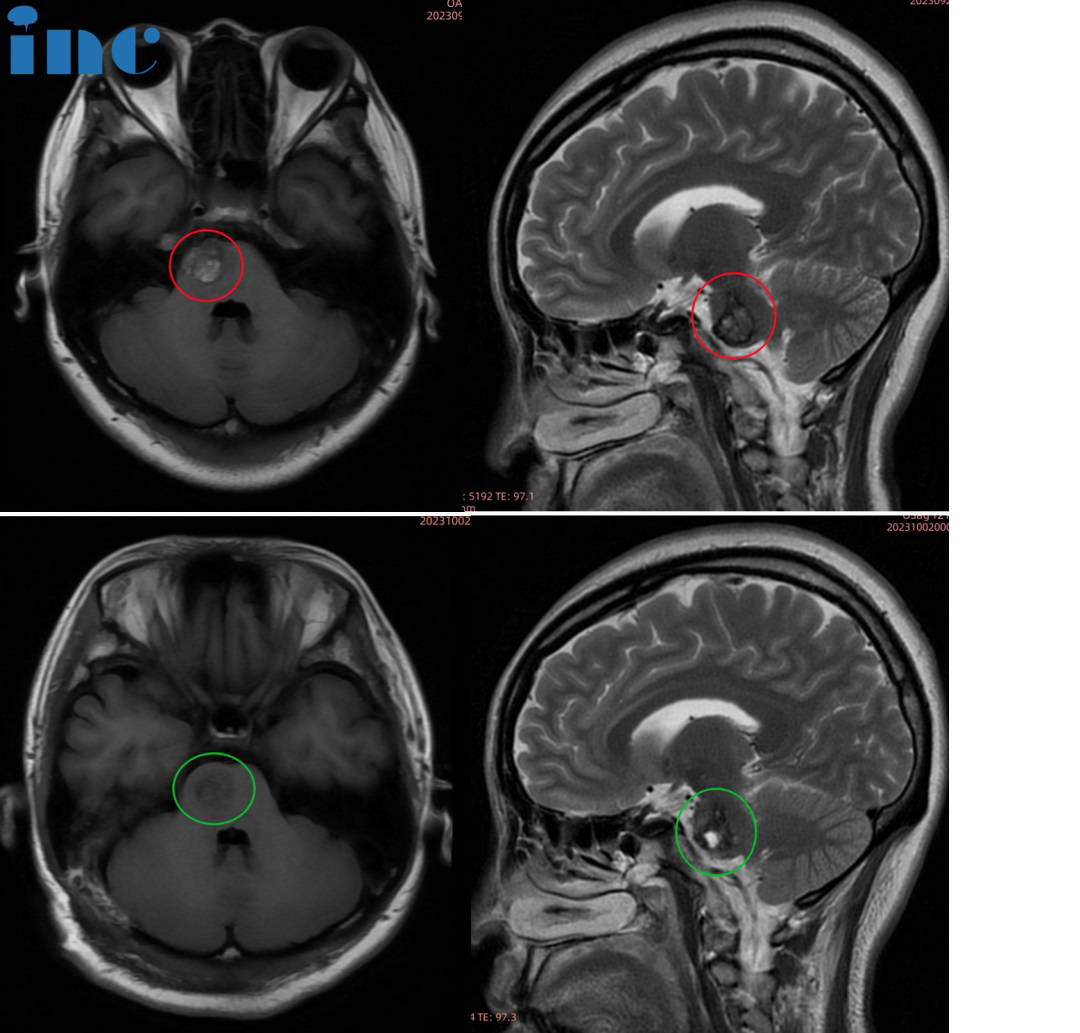

30岁男性-脑干(桥脑)海绵状血管瘤

病史摘要:“从2016年1月份开始,头晕、行走不稳,重影复视。2016年至2018年,我大概有4次出血。18年到现在,出血有3次……”30岁的江先生罹患脑干海绵状血管瘤,血管瘤已经从四脑室鼓出来,一旦再次大量出血,可能带来不可预知的较大风险。手术是的解决办法,但江先生的父母更加担心的是,“我们就是怕手术有后遗症,他还没结婚。从他生病之后,我和他爸爸较担心这个。”

▼脑干海绵状血管瘤术前MRI

治疗过程:2023年11月5日,巴教授为江先生成功手术,脑干海绵状血管瘤得到顺利全切。

术后情况:

术后1天查房,转出ICU,转入普通病房,恢复状况良好。巴教授查房时用中文询问道“今天感觉怎么样?”“Very very good!”,巴教授逐一检查了江先生的吞咽、面部活动、肢体活动等功能,“没问题”,巴教授为江先生的状态点赞。“Thank you very much!”,江先生及家人都无比感谢巴教授。

术后2天查房,江先生的眼睛已经比术前好一些了。术后两周江先生顺利出院。